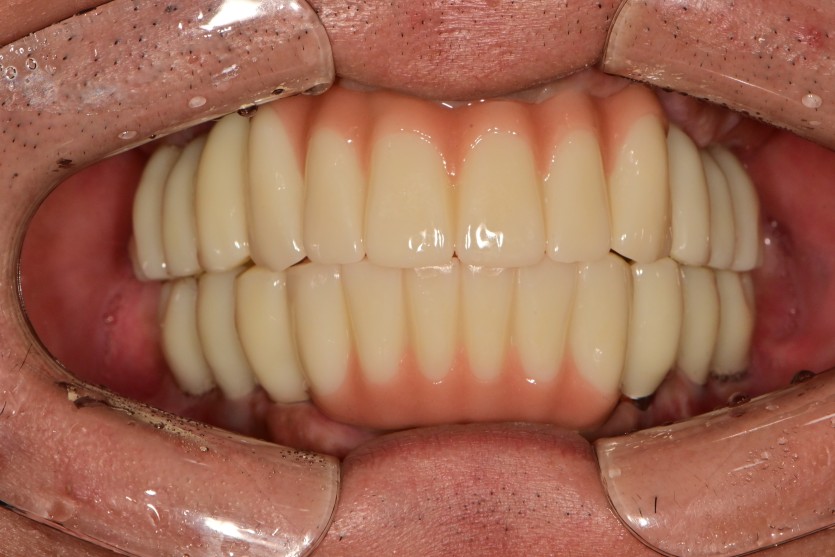

만 36세 전체 임플란트 증례

전체 임플란트 증례입니다.

18개의 임플란트로 완성하였습니다.